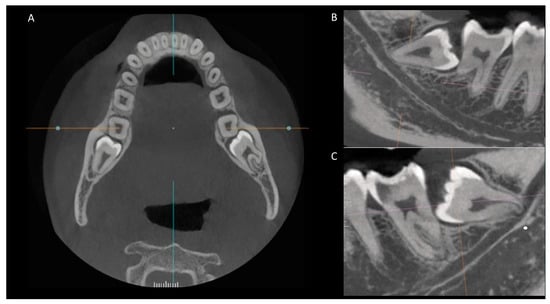

2. Materials and Methods

3.3. Anatomical Relationship between the Root Apex of the Impacted Third Molar and the Mandibular Canal